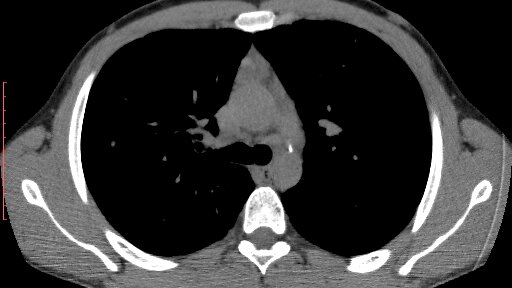

Если пациент пришел на приём к врачу-онкологу, значит, для верификации диагноза необходимо провести обязательные исследования. И первое, куда направляется пациент – это компьютерная томография с контрастом (КТ с контрастом). Для чего это нужно? Давайте разбираться. Эта высокоточная диагностическая методика предполагает внедрение в организм препарата, в составе которого присутствуют йод или барий. Он не вредит организму и спокойно выводится за 24 часа. Но задерживает рентгеновские лучи и позволяет...

КТ с контрастом – это современный способ обследования, применяемый в целях обнаружения различных нарушений в функционировании внутренних органов. Такую диагностику применяют для выявления патологий в головном мозге, брюшной полости, легких. Что такое КТ с контрастом Компьютерная томография с контрастированием является самым эффективным способом оценки состояний сосудов и полых органов. Диагностика выполняется на современном оборудовании, представляющем собой мощные томографы. Для повышения четкости снимков прибегают к контрастированию...